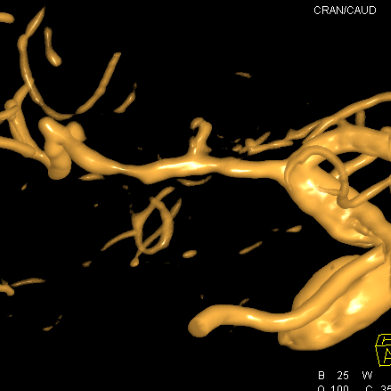

重建的形态

血管直径测量

血管形态

放大后仔细观看,近端有局限性血管变细,并见双腔征

另外时相远端也隐约局限性变细